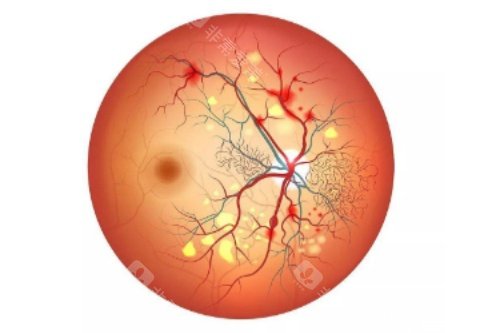

作为首都医学大学附属北京同仁医院眼底病科的“定海神针”,他擅长复杂眼底病诊疗,尤其对视网膜脱离、糖尿病视网膜病变等疾病的手术处理堪称业内标杆。